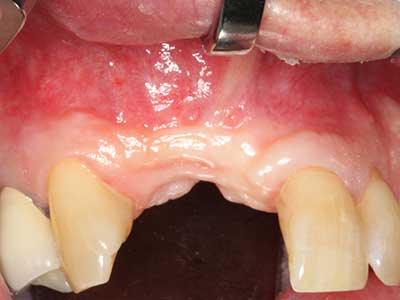

Bone tissue is not simply a mineral structure but also contains a substantial proportion of collagen fibres. This means it not only has good compressive strength but also a degree of flexibility, which can be taken advantage of when performing bone augmentations. In the classical expansion procedure using bone splitting, the atrophied alveolar ridge is split longitudinally and carefully expanded after reaching an adequate osteotomy depth (Fig. 13-16), ideally without substantial removal of the periosteum (Brugnami, Caiazzo et al. 2014, Stricker, Fleiner et al. 2014). Screw and plate systems with increasing expansion distance have proven effective in separating the two bone lamellae while remaining below the fracture threshold. In general, residual bone widths of at least 3–4 mm are required (Chiapasco, Zaniboni et al. 2006) to guarantee adequate flexibility and sufficient bone coverage of the future implants. If necessary, a vertical relief osteotomy on one or both sides can improve flexibility. A combination with additional augmentation techniques, particularly on the buccal side, has been described as an alternative to the classical technique.